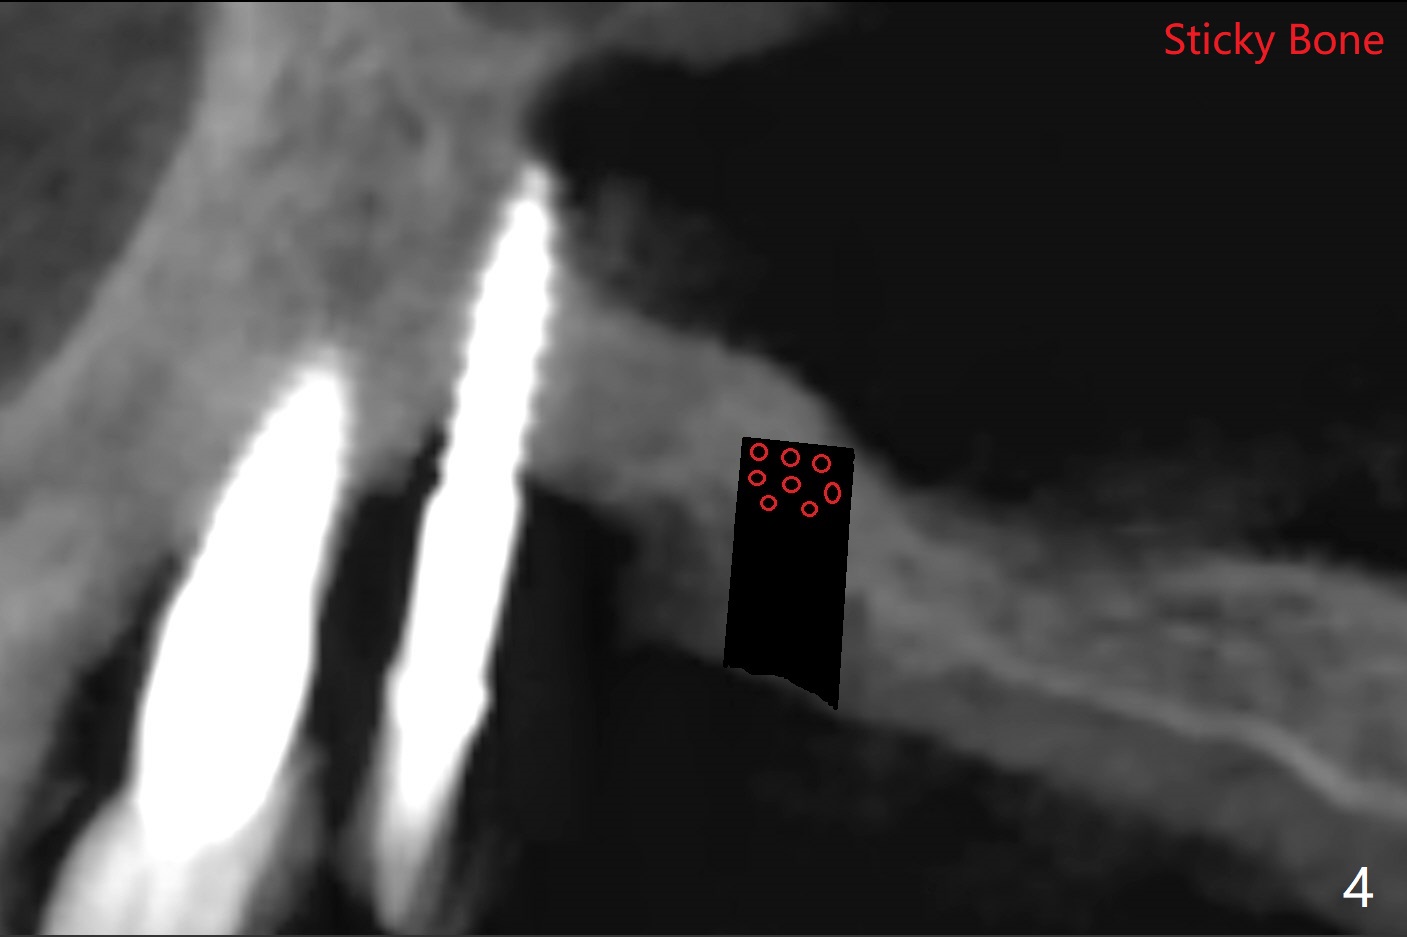

术前清晨复习3号牙窦底,中央是植骨(图一,二:*(皮质骨:密度高,质地可能软)),由于窦底斜坡,术前估计穿孔可能最先发生在远中,术中的确如此(图三:<(使用4毫米钻头后)),放置粘性骨粉(图四),利用导板(图五:G)和4x9毫米报废植体提升(*)。使用4.5毫米钻头,放置半张PRF膜,骨粉,5x7毫米植体以及修复基台,最后在后两者周围放置骨粉(图六,七:*(腭侧一个螺纹暴露)),覆盖1/2PRF膜,缝合,树脂敷料。